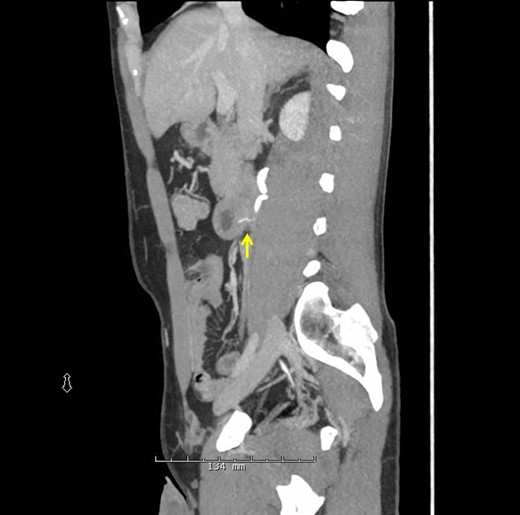

A 38-year-old male presented to the hospital with a chief complaint of abdominal pain and hematuria 1 day after eating a barbecue pulled pork sandwich. He described the pain as ‘deep’ in his abdomen, sharp and non-radiating with no episodes of nausea, emesis or diarrhea. He denied any dysuria or frequency. The patient's past medical and surgical history was unremarkable. He had no abnormalities on his laboratory values besides a urinalysis demonstrating 2+ blood and 11–24 RBCs/hpf. Physical examination revealed point tenderness to deep palpation to the right of his umbilicus, but his abdomen was soft with no signs of peritonitis. An upright abdominal X-ray was unremarkable; however, a CT of his abdomen demonstrated a 2-cm linear density representing the FB in the posterior third portion of the duodenum perforating into the retroperitoneum abutting the right ureter causing hydronephrosis (Figs 1 and 2, arrow). Two separate attempts were made at endoscopic retrieval in the first 24 h without successful visualization or removal of the FB. Due to the ureteral involvement and hydronephrosis, an operative intervention was recommended.

Sagittal CT scan again demonstrating the FB through the posterior wall of the duodenum onto the anterior surface of the ureter.